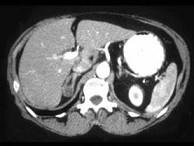

问题 女,35岁,无意中发现血压高,实验室检查:血和尿中醛固酮水平增高,请结合所提供图像,作出诊断()

选项 A.右肾上腺增生 B.右肾上腺Cushing腺瘤 C.右肾上腺皮质腺瘤 D.右肾上腺转移瘤 E.右肾上腺囊肿

答案 C